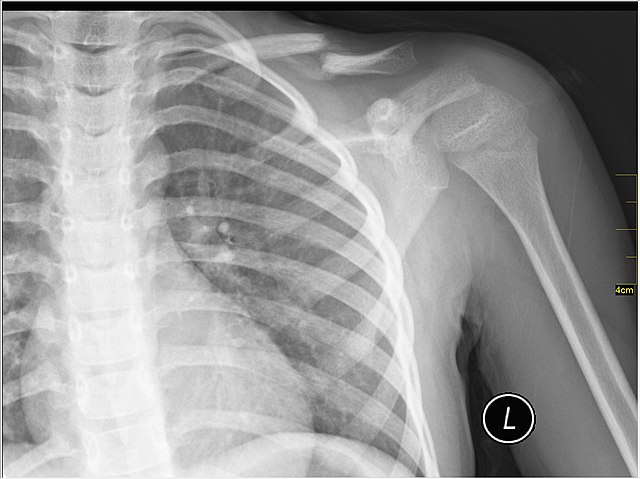

Example 3

Diagnosis

Pneumoperitoneum

Image 3:640px-Pneumoperitoneum_modification.jpg author?